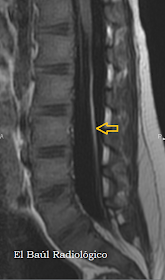

FIGURA 5) Imagen FSE-T1. Lipoma filiforme del Filum que produce un síndrome de médula anclada y descenso del cono medular. Aparece como un cordón hiperintenso.

FIGURA 1) Imagen FSE-T1. Lipoma filiforme del Filum (flecha). Aparece como un cordón hiperintenso.